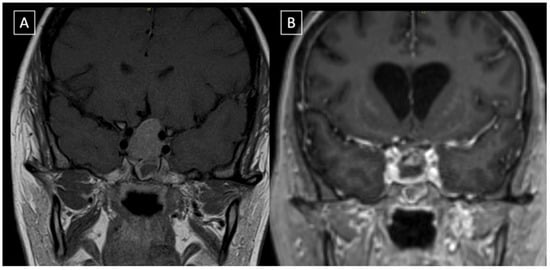

2. Case Presentation